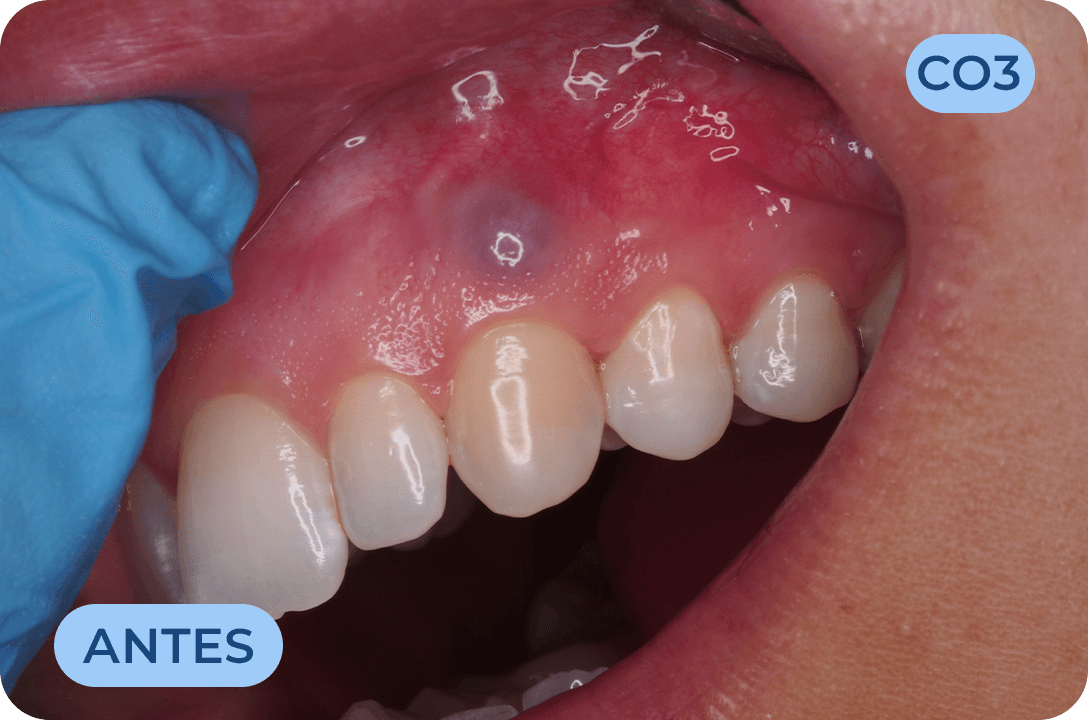

Cirurgia Oral

Área da medicina dentaria que diagnostica e trata as lesões e anomalias dos dentes, tecidos moles e estruturas anexas aos maxilares. A extração de dentes irrecuperáveis, dentes inclusos, supranumerários, frenectomias (eliminação dos freios), biopsias, exérese de quistos e outras lesões dos tecidos orais, fazem parte do seu vasto campo de execução.